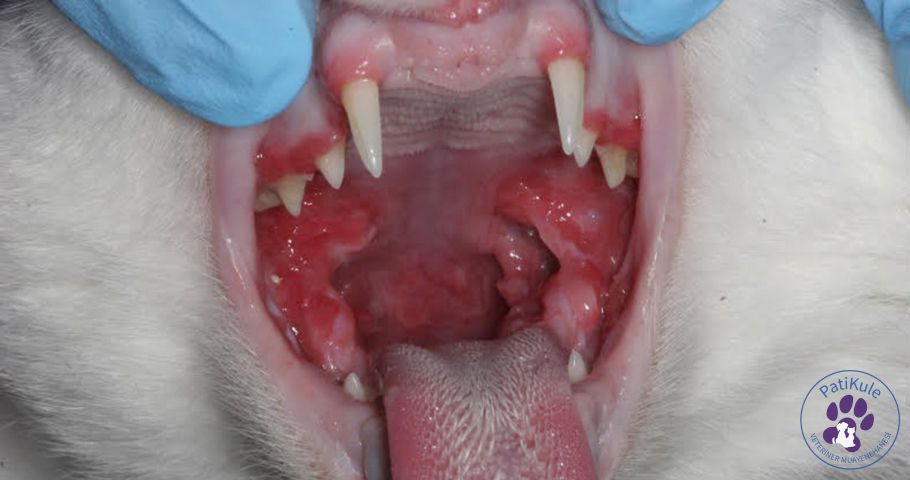

Kedilerde kaudal stomatit ya da caudal stomatitis farklı nedenlere bağlı olarak görülmektedir. Ağız yarası ve enfeksiyonları anlamında kullanılan bu ifade, ağız bakımının iyi yapılmadığı durumlarda ortaya çıkmaktadır. Kedinizin ağzında yara bulunuyorsa ve bu yaraya iyi bakılmadıysa kısa sürede stomatit görülebilir. Stomatit ağız bölgesinin geniş kısmında ortaya çıkar. Genel olarak ise ağız kenarı, dil, damat, iç yanak ve diş etlerinde görülmektedir.

• Genel olarak önemli bir belirti diş eti renginde meydana gelen değişimdir, diş eti rengi kırmızıya döner.

• Çatlamış şekilde görünen diş etleri.

Kaudal stomatit oluşumu için tek bir neden bulunmaz. Özellikle tıbbi açıdan da kesin bir sebep yoktur. Genel olarak ise ağızda meydana gelen yaraların büyümesi, enfeksiyon kapması ve bunun sonucunda da hızla yayılması neden gösterilmektedir. Ayrıca uzmanlar bağışıklık durumuyla da yakından ilişki kurmaktadır. Bağışıklığı zayıf olan kedilerde stomatit çok daha sık ve yaygın görülür. Dişlerdeki tartar ve çürük gibi sorunlar da stomatit oluşumunu tetiklemektedir.